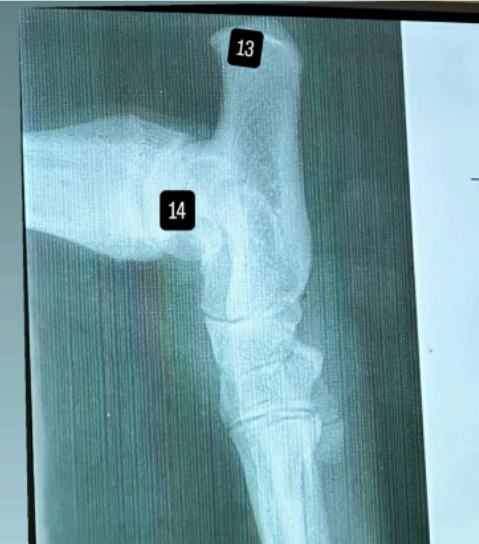

czym jest dysplazja stawu łokciowego?

Dysplazja stawu łokciowego to wrodzona lub rozwojowa wada, w której elementy tworzące staw łokciowy (kość ramienna, łokciowa i promieniowa) nie pasują do siebie prawidłowo.

W zdrowym stawie powierzchnie stawowe są idealnie dopasowane i równomiernie przenoszą obciążenia. W dysplazji dochodzi do zaburzeń ich kształtu lub synchronizacji wzrostu kości, co powoduje nierównomierne rozłożenie sił w stawie.

jakie są 4 jednostki chorobowe wpływające na dysplazję stawu łokciowego?

FCP – oddzielony/rozfragmentowany wyrostek dziobiasty przyśrodkowy kości łokciowej

UAP – brak zrostu wyrostka łokciowego dodatkowego (anconeal process), który pozostaje oddzielony od kości łokciowej.

OCD – oderwanie fragmentu chrząstki i kości w obrębie kłykcia przyśrodkowego kości ramiennej.

INC – niezgodność powierzchni stawowych, czyli zaburzenie prawidłowego dopasowania kości tworzących staw łokciowy.